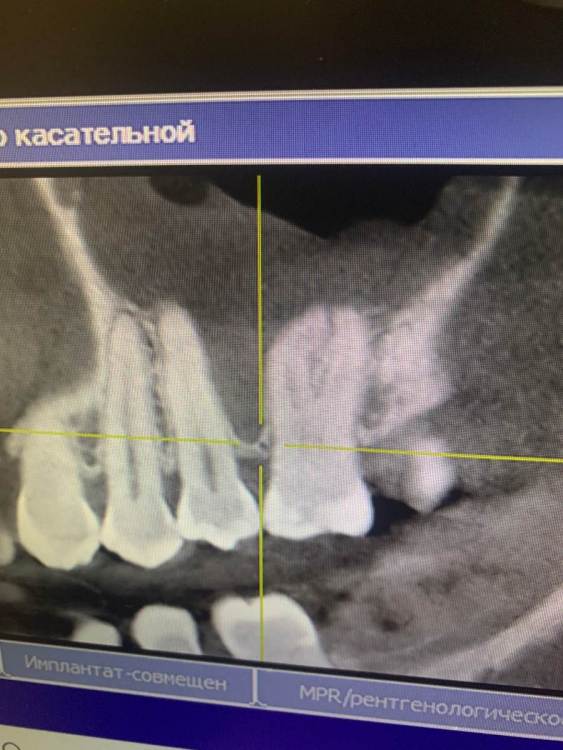

KOCTb Опубликовано 1 января, 2024 Поделиться Опубликовано 1 января, 2024 Здравствуйте коллеги. Может кто-то подскажет полезного. Пациентка. Лет 6 назад пришла с симптоматикой пульпита во втором секторе. На некоторых зубах были пломбы, без криминала. Зубы были проверены на витальность. Все живые. Пальпаторно передняя стенка ВП давала лёгкую чувствительность. Сделали КТ. Апикальных изменений не выявлено, а в пазухе слева признаки гайморита. Заполнена была бальше чем наполовину. Отправил к ЛОРу. Пролечили. Анатомическое строение не очень понравилось. С тех пор каждую зиму у неё обострение ВЧ синусита слева. Иногда даже два раза бывает. Каждый раз ЛОР в направляет к стоматологу и говорит, что гайморит одонтогенгый. Врачи рентгенологи в описании иногда там находят одонтогенгую кисту… Года два назад пациентка сходила поменяла все пломбы, на всякий пожарный. Со слов зубы все были витальные при лечении. Ну и собсвенно опять ВЧ синусит. Смущает анатомическое строение между 25 и 26 зубом. Не может ли там через периодонтальную щель «сифонить» ? Говорит между зубами иногда какой-то дополнительный дискомфорт есть. Ссылка на комментарий

Astronaft Опубликовано 14 января, 2024 Поделиться Опубликовано 14 января, 2024 Здравствуйте. 6 лет назад: подробнее про симптомы пульпита? как полечили гайморит и чего добились? Анатомия действительно интересная. Интуитивно, или естественная впадина которая способствует застою либо проблемы в соустье вызывают застой и кислотный секрет лизирует самое слабое место. Опять же интуитивно, пациентке приказать зубы не трогать, не ходить выискивать проблемы. Очень подробно расспросить анамнез, в том числе что помогает, что запускает синусит. Если соустье открыто то я бы рекомендовал регулярно промывать физраствором с ЭДТА и выждать. Ссылка на комментарий

KOCTb Опубликовано 15 января, 2024 Автор Поделиться Опубликовано 15 января, 2024 19 часов назад, Astronaft сказал: Здравствуйте. 6 лет назад: подробнее про симптомы пульпита? как полечили гайморит и чего добились? Анатомия действительно интересная. Интуитивно, или естественная впадина которая способствует застою либо проблемы в соустье вызывают застой и кислотный секрет лизирует самое слабое место. Опять же интуитивно, пациентке приказать зубы не трогать, не ходить выискивать проблемы. Очень подробно расспросить анамнез, в том числе что помогает, что запускает синусит. Если соустье открыто то я бы рекомендовал регулярно промывать физраствором с ЭДТА и выждать. Здравствуйте. Ну как обычно пульпитная симптоматика при ВЧ синусите. Разлитые периодические боли в верхнем секторе, с непонятной локализацией. Пальпаторно передняя стенка ВЧ пазухи давала болезненность. От 25 до 27 зуба. На КТ зубов затенение в ВЧ пазухе. Отправил тогда к ЛОРу. Подробности лечения у ЛОР врача тогда не знаю. Синуситы в холодное время года. Соустье пародонтальным зондом не выявлено. Носо-ротовая проба также отрицательная. Но тут и понятно если и есть ход, то крайне мизерный. Там слизистой завалено всё. Ссылка на комментарий